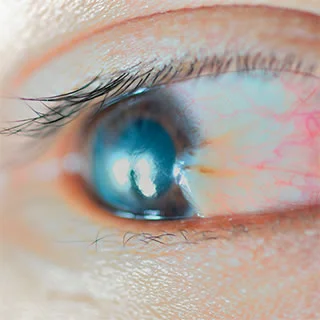

A pterygium is a small triangular shaped growth that occurs on the front surface of the eye.

It starts on the white part of the eye (the outer lining called the conjunctiva) and then grows onto the cornea – the usually clear front surface of the eye.

It is caused by exposure to ultraviolet rays from sunlight and is therefore is more common in people who work outdoors or spend a lot time in the sun. Sometimes a pterygium causes eye irritation or redness. Rarely it grows to the centre of the cornea to causing blurred vision. The only way to treat a troublesome pterygium is to surgically remove it, which is normally performed under local anaesthetic.